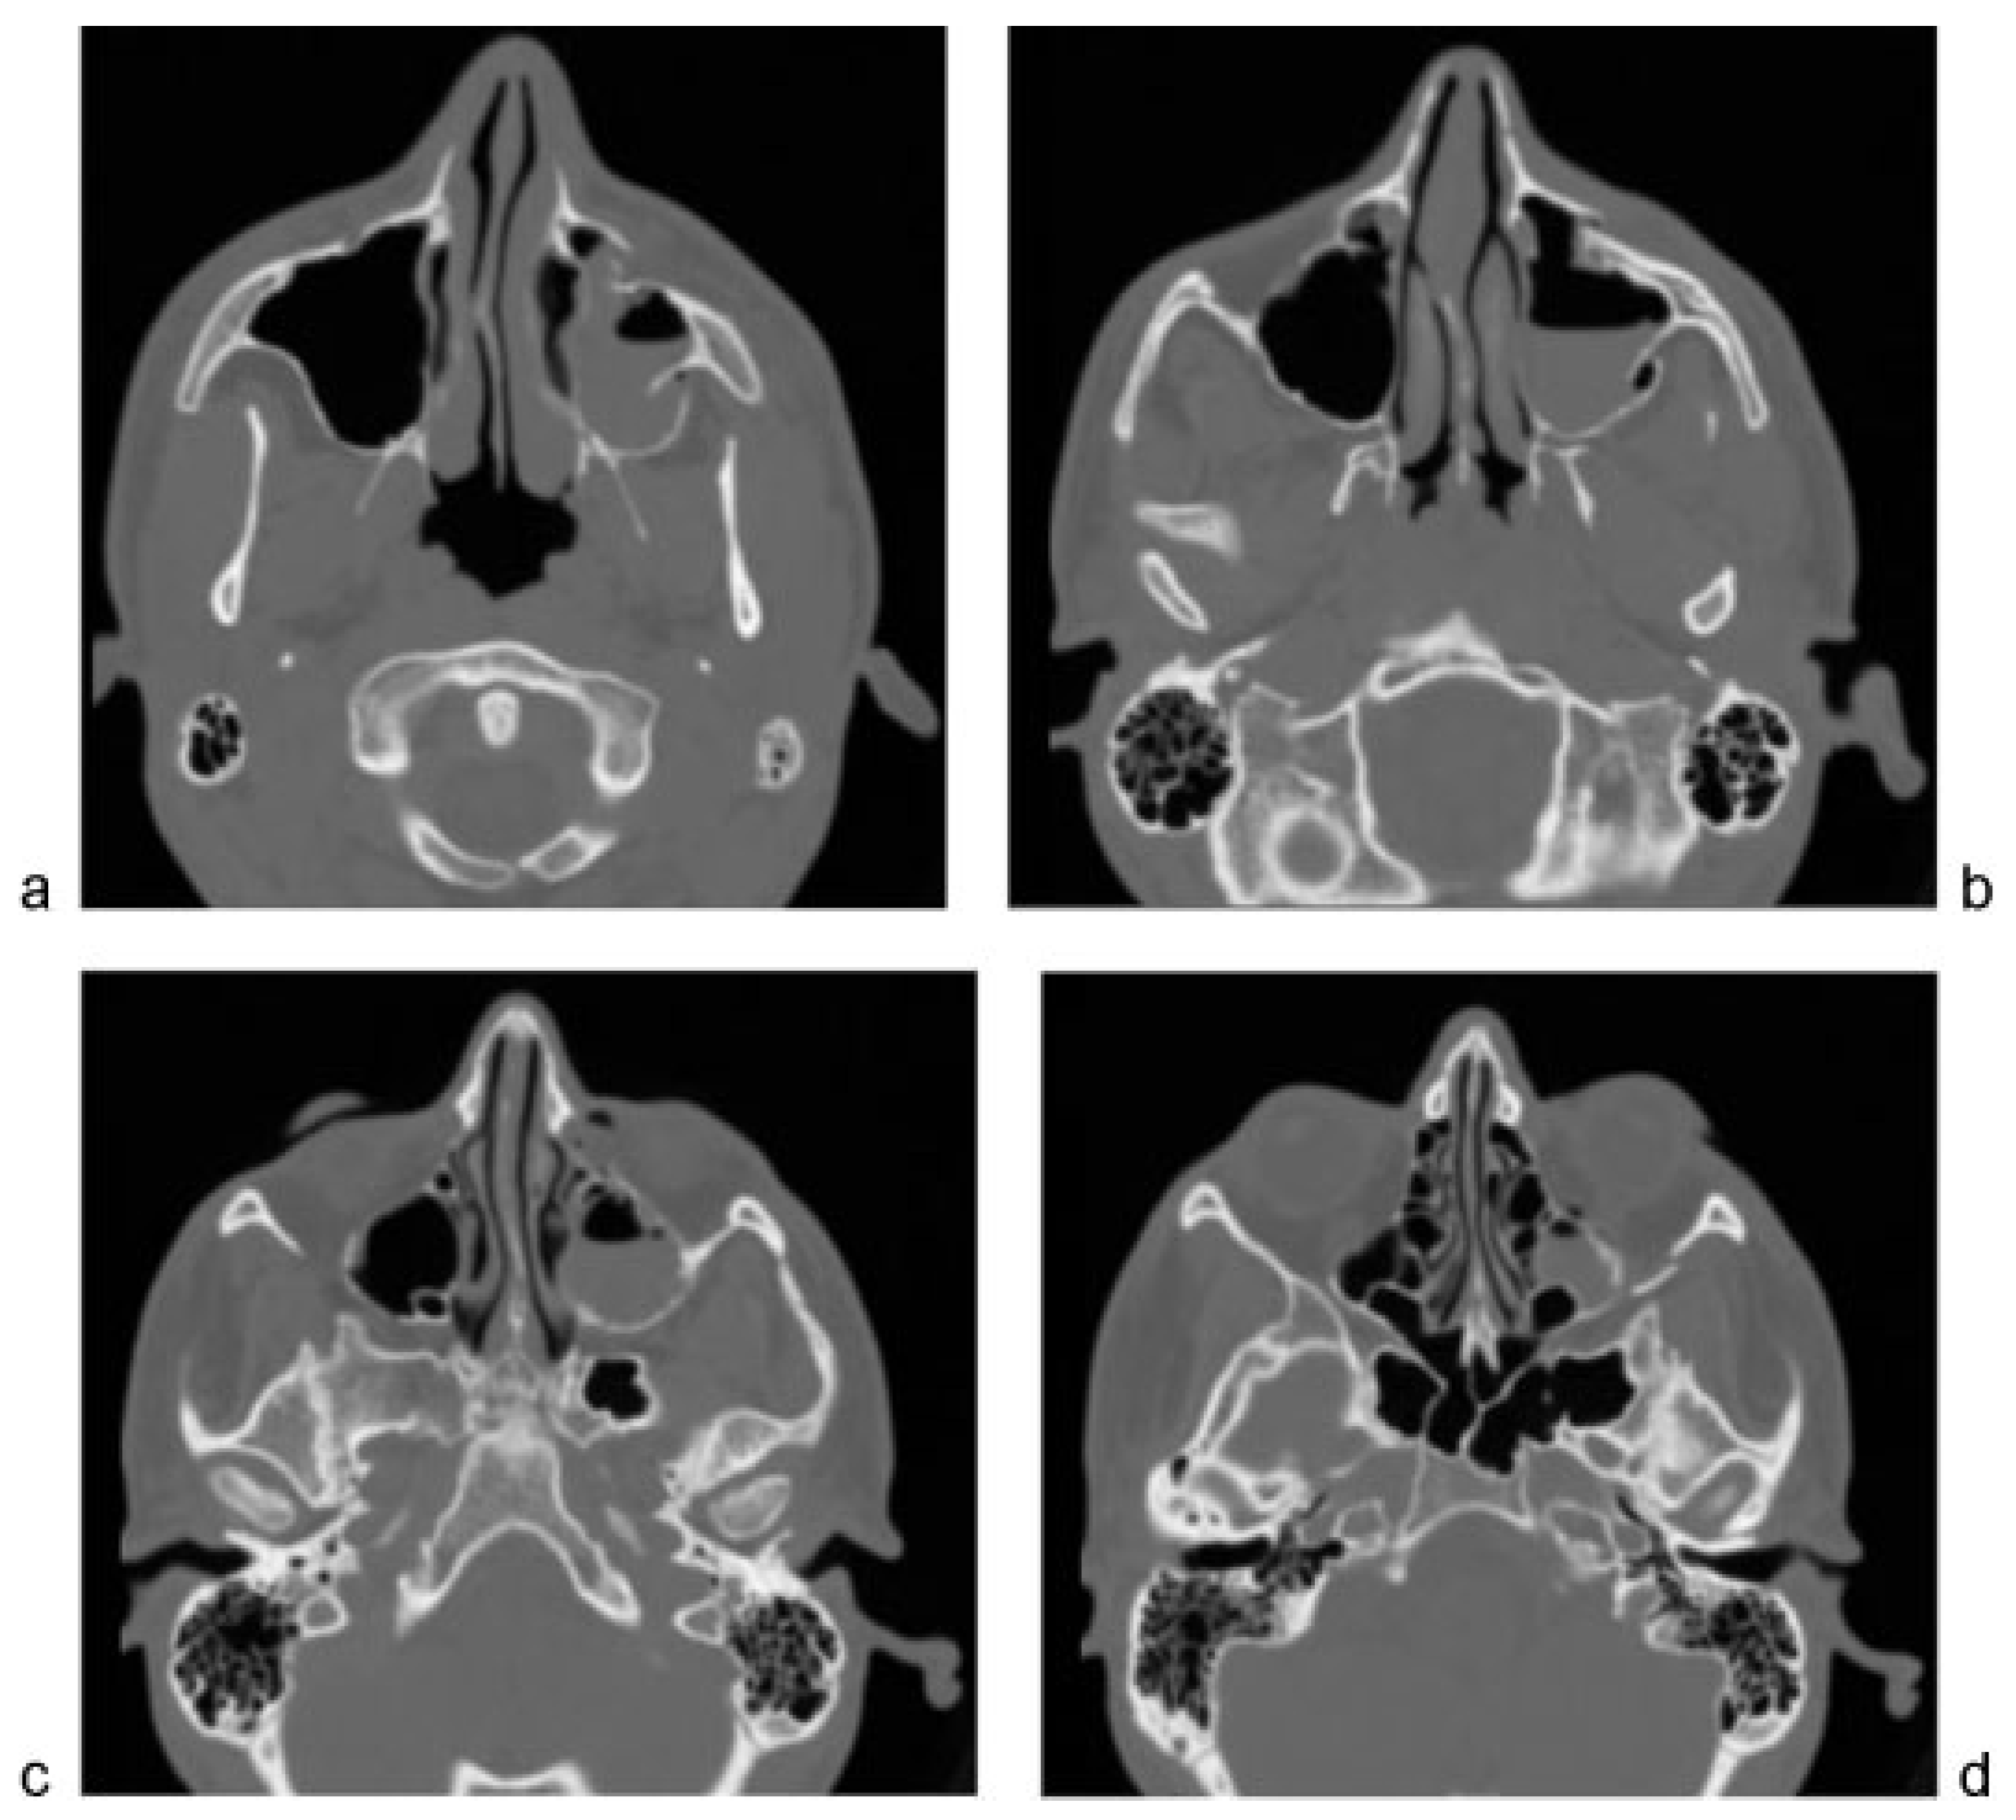

Postoperative imaging demonstrated anatomic reduction of the OZMC at all articulations (Figure 7 and Figure 8).

Figure 7. Postoperative maxillofacial computed tomography. The orbitozygomatic complex is anatomically reduced, with excellent alignment at the (a,b) zygomaticomaxillary buttress, at the (c) sphenozygomatic suture, (df) orbital floor, and (g) frontozygomatic suture.